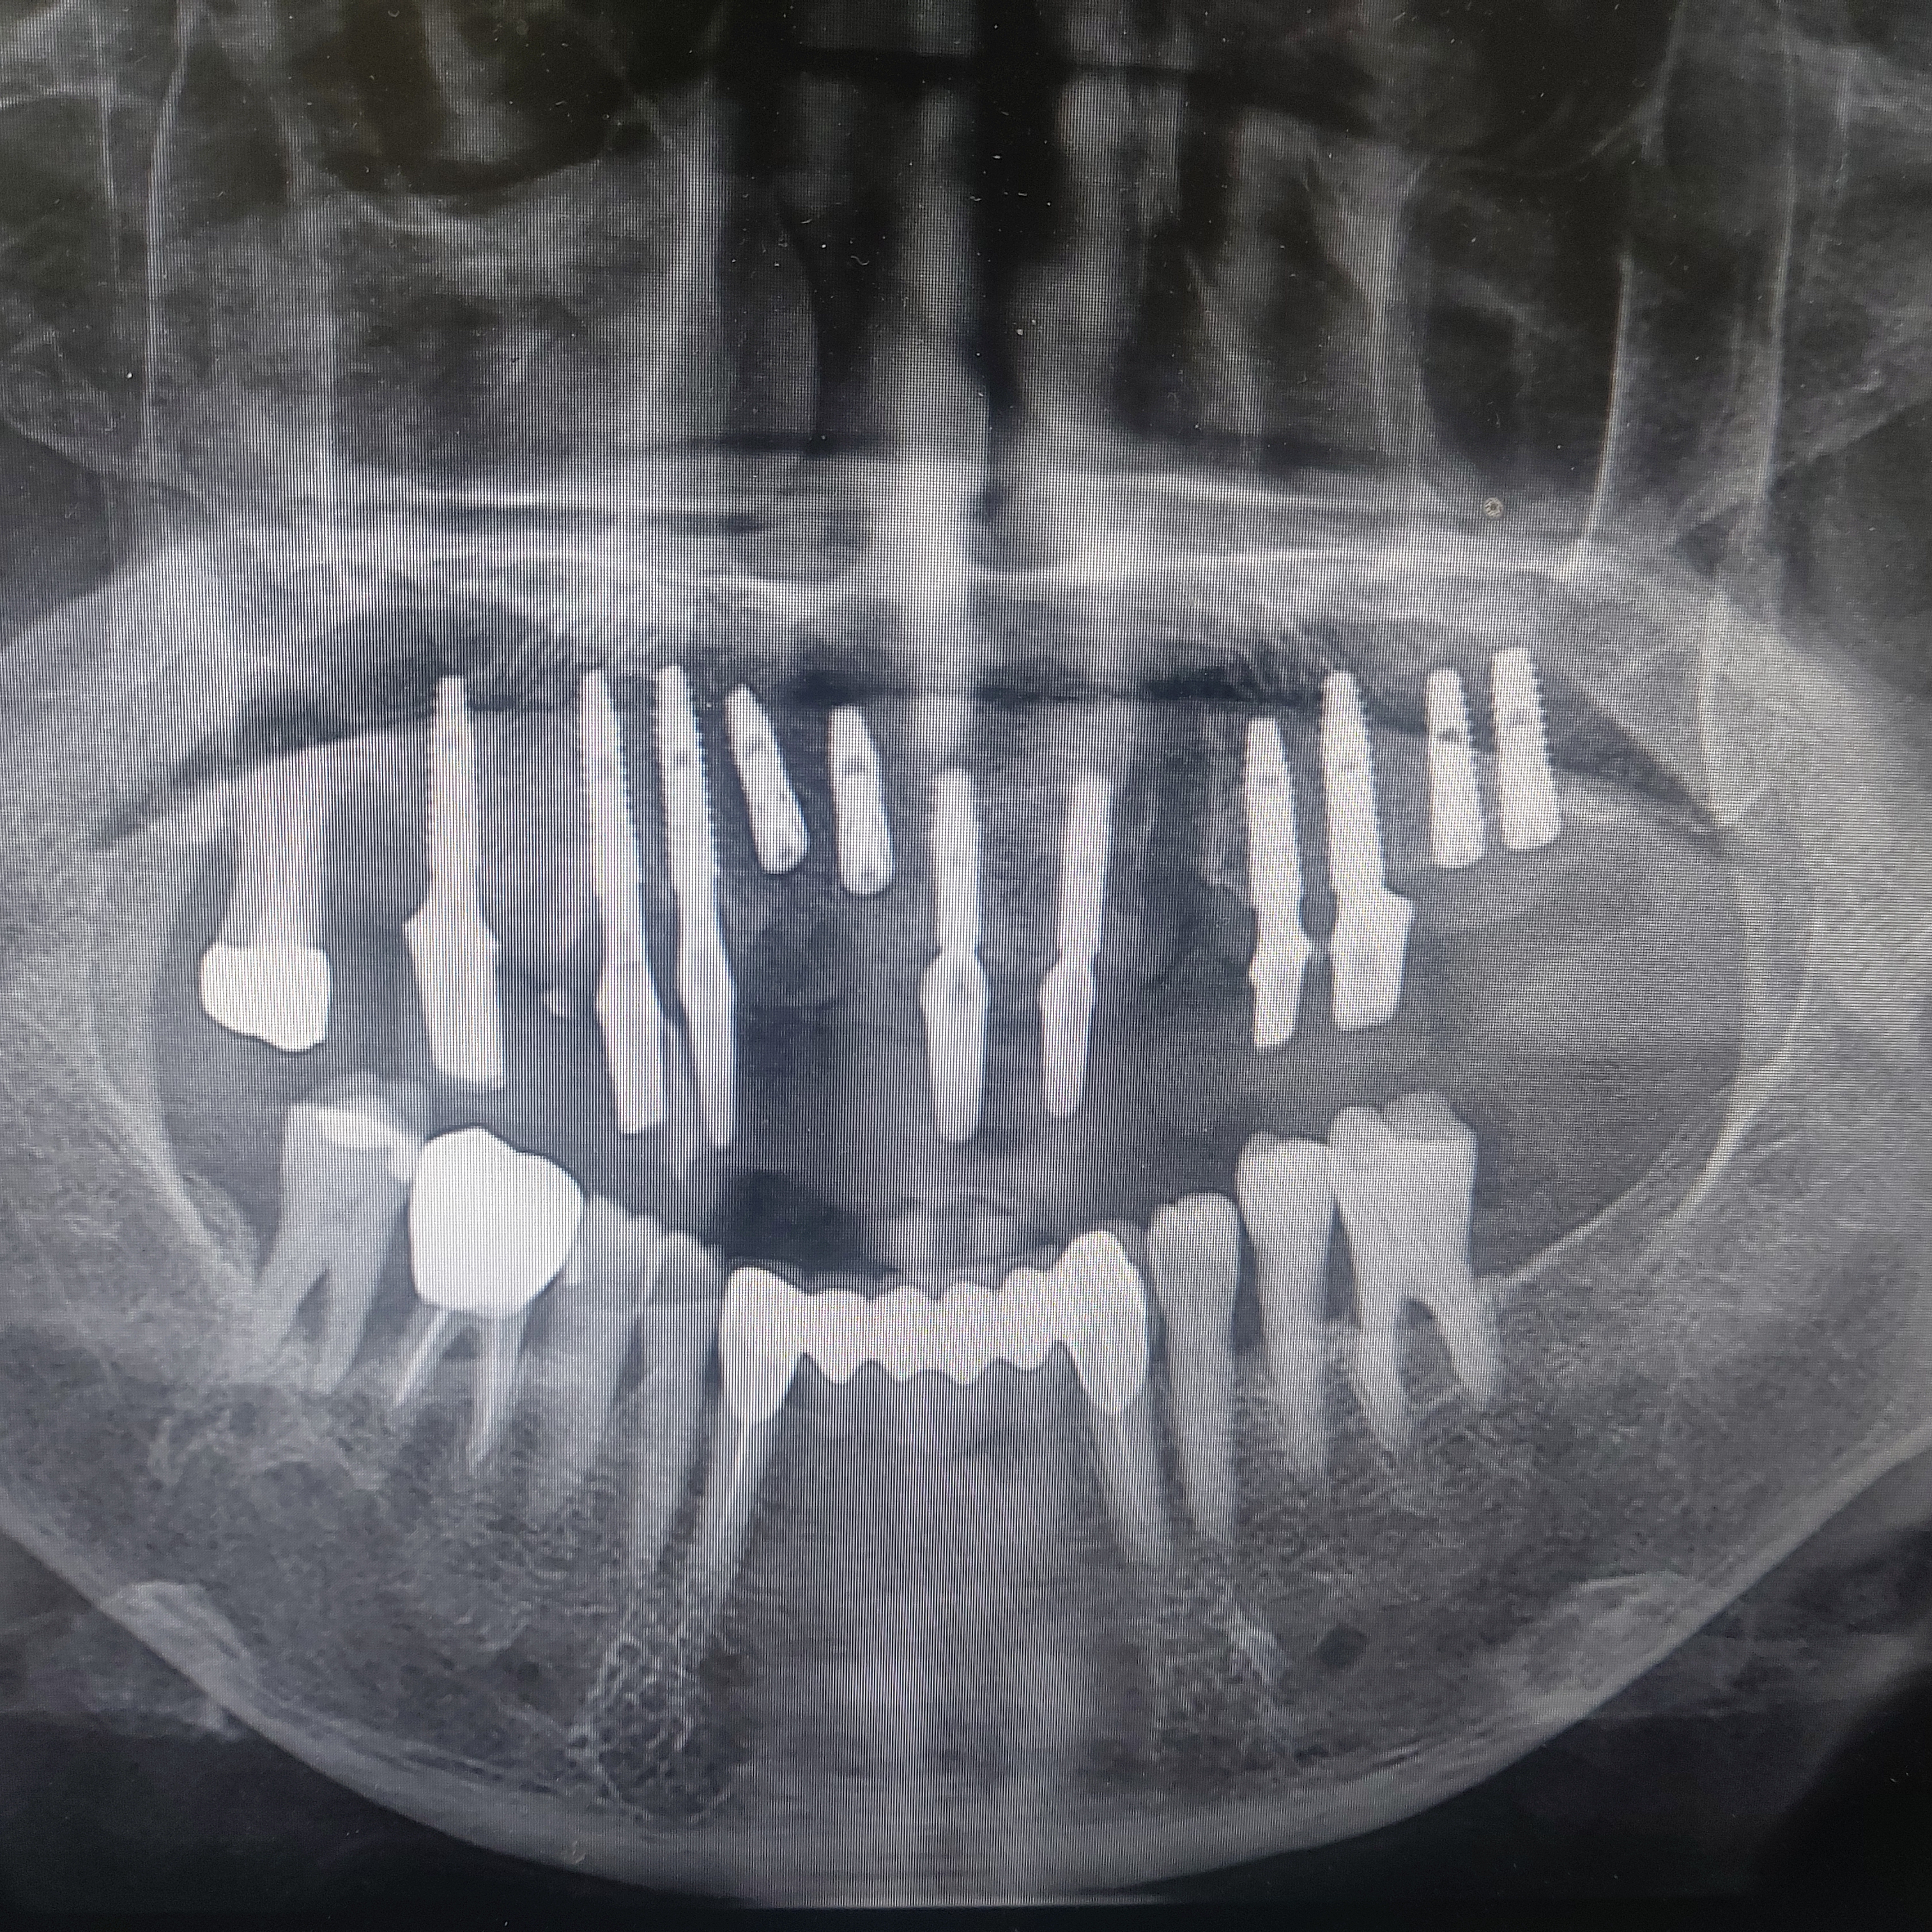

이번 환자분은 70대 중반의 비교적 고령 환자분으로 위앞니가 불편함을 주소로 내원하셨습니다.

저는 기존 치아를 남겨두고 나머지만 치료를 하는 방어적인 치료를 귄해 드렸지만 환자분은 지금 앞니가 불편하고 어짜피 해야될꺼 다 뽑고 임플란트로 진행하고 싶다고 말씀하셨습니다.

결국 17번치아(상악 우측 제 2대구치)를 우선 남겨서 환자분의 교합고경에 이용하였습니다.

발치를 시행하고 최대한 많은 수의 임플란트를 식립하고 초기 부하가 나오는 곳에 지대주를 연결하고 임프레션 코핑을 이용하여 인상을 채득하였습니다.

꼭 저렇게 많이 심어야되??

저는 상악 기본 8개만 비용을 받고 있습니다.

추가 식립은 혹시 모를 즉시 부하로 인한 실패에 대비하기 위함입니다. 추가 식립 비용은 없습니다.

기존 지대주가 임플란트 실패가 한 두개 생기더라도 나머지 묻어 두었던 임플란트를 사용하기 위함입니다.